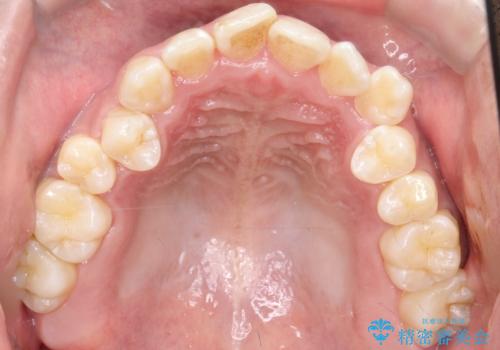

- 左上の八重歯を気にされて来院されました。精密な検査の結果、歯列全体を広げながら八重歯を奥へ移動させることで、美しい歯並びと機能的な咬み合わせが得られると診断。患者様のご希望に合わせ、透明で目立ちにくい**インビザライン(マウスピース矯正)**による治療計画を立案しました。抜歯を避け、歯を少しずつ遠心(奥)へ移動させることで、歯が並ぶスペースを確保し、叢生(歯のデコボコ)を改善します。

今回の矯正治療では、透明なマウスピース型の装置インビザラインを使用しました。この装置は目立ちにくく、取り外しが可能なため、食事や歯磨きも普段通りに行えます。遠心移動という方法で奥歯を後方に動かし、前歯を並べるためのスペースを確保。これにより、抜歯することなく、左上の八重歯を含む叢生を効果的に改善し、整った美しい歯並びと良好な咬み合わせを獲得していただけました。